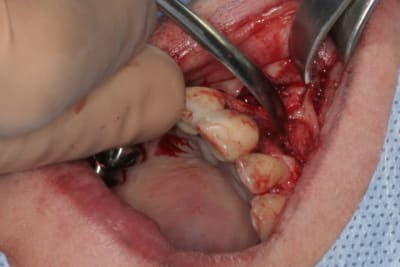

tien, ce matin, extraction de 24/25, curetage méticuleux, forage, comblement du gap, pose des 2 implants qui se sont bloqués à 50Ncm au CA sur les 3 ou 4 mm apicaux, pose des vis de cicat, sutures...35min....tranquille...

Purée, tu prends des risques énormes en fourrant ton bio oss puis en vissant les implants dans la masse de bio oss, de un, et sans membraner l'interface pilier implant, de deux...

Je suis peut-être vieux jeu mais c'est, à mon avis, dangereux d'un point de vue bactériologique.

c'est pas la première fois que je fais çà...;-)

et çà me donne plutôt de bons résultats

après tout...le périoste n'est-il pas la meilleure membrane?

par contre il faut veiller à avoir une bonne étanchéité au niveau des sutures...